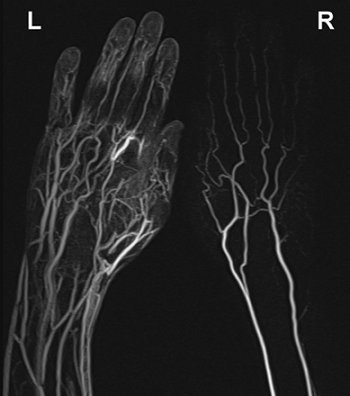

| Maximum intensity projection from reconstructed 3D contrast-enhanced MR angiography of both hands of 25-year-old healthy male volunteer after IV administration of gadobutrol using a flow rate of 0.5 mL/sec. Imaging sequence was obtained 40 seconds after initiation of contrast injection. Subsystolic cuff compression is applied to upper arm on right side. Major venous contamination (venous contamination score = 2) is observed on noncompressed left side. Gluecker TM, Bongartz B, Ledermann HP, Bilecen D. "MR Angiography of the Hand with Subsystolic Cuff-Compression Optimization of Injection Parameters" (AJR 2006; 187:905-910). |

Upper arm compression was applied unilaterally with a standard blood pressure cuff during all three studies. "Subsystolic compression was performed with a pressure value of 30% less than the brachial artery systolic blood pressure measured by the examination," the authors explained. The volunteers received 0.1 mg/kg dose of gadobutrol followed by a saline flush for each 140-second-long study.

All 10 subjects completed the exams and tolerated the cuff compression, the authors stated in their results. For all three flow rates, a contrast-to-noise ratio (CNR) of more than 10 was obtained. In the venous vessels, the least venous contamination was measured with a flow rate of 0.5 mL/sec.

On qualitative analysis, this latter flow rate starting at 60 seconds was given the highest score by the reviewers. Conversely, studies performed with an injection rate of 1.5 mL/sec received the worst score for venous contamination.

Diminished venous contamination was seen on the compressed side for all flow rates, the group reported. Again on qualitative analysis, both reviews saw less venous contamination on the compressed side and with a flow rate of 0.5 mL/sec.